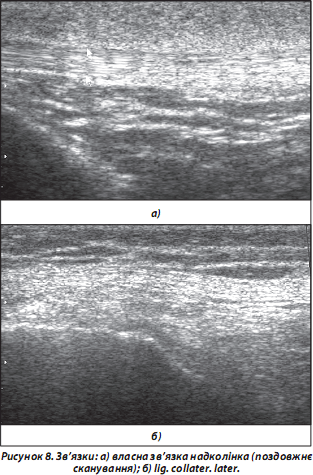

8. Зв’язки за ехоструктурою подібні до сухожиль. При УЗД виглядають, як:

а) гіперехогенні фібрилярні структури (власна зв’язка надколінка, lig. collater. med. тощо) (рис. 8а);

б) змішані фібрилярні структури (lig. collater. lat. тощо) — за рахунок контралатерально спрямованих волокон (рис. 8б);

в) гіпоехогенні структури (ligg. cruciata ant. et post., інші фрагменти внутрішньосуглобових структур) — за рахунок неперпендикулярного розташування ходу УЗ-променя.